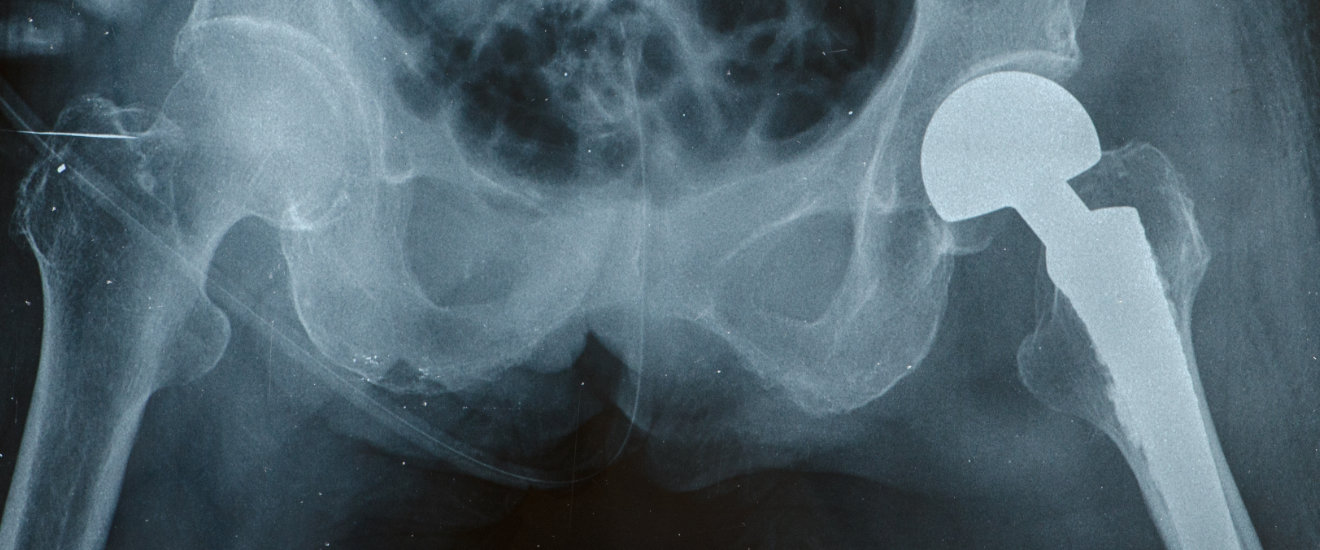

Wie gut müssen die Argumente sein, wenn ein Patient ein – für ihn ungünstiges – medizinisches Sachverständigengutachten entkräften will? Ein aktueller Beschluss des BGH macht Mut. Pro Jahr erhalten in Deutschland rund 200 000 Menschen ein künstliches Hüftgelenk. Ob die OP ein Erfolg [...]